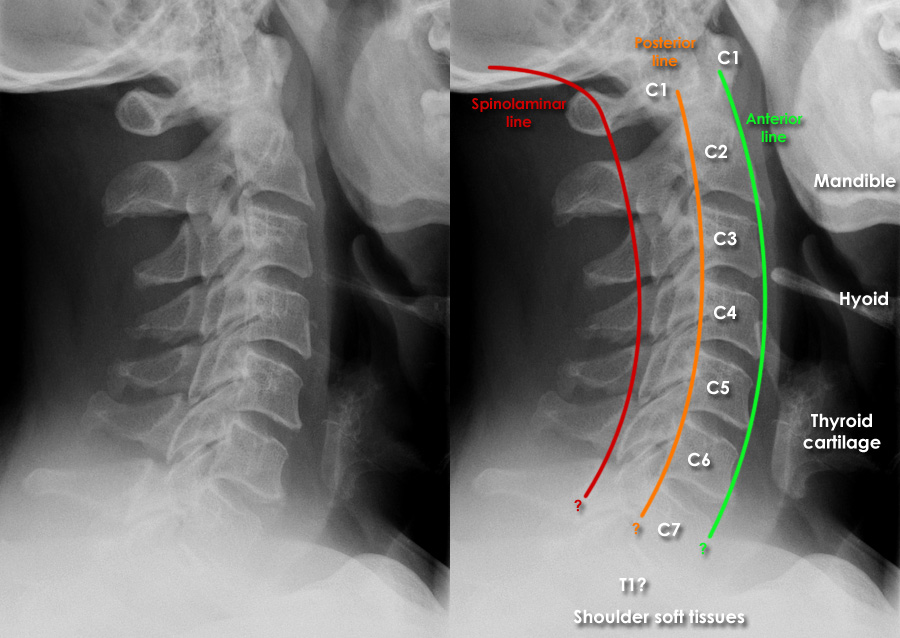

The X ray cervical spine AP lat is a comprehensive radiographic examination that visualises the cervical spine, which includes the first seven vertebrae (C1-C7). This cervical spine X ray is crucial for identifying and evaluating various conditions affecting the bones, joints, and soft tissues of the neck. The AP (anteroposterior) view involves taking an X-ray from the front to the back of the patient, while the lat (lateral) view captures the spine from the side. Together, these views provide a thorough assessment of the cervical spine, helping doctors diagnose a range of conditions, plan treatments, and monitor the progression of diseases or the healing process after surgeries.

The X ray cervical spine AP lat is used to diagnose and evaluate a wide range of conditions affecting the cervical spine. Some of the most common reasons for recommending this test include: